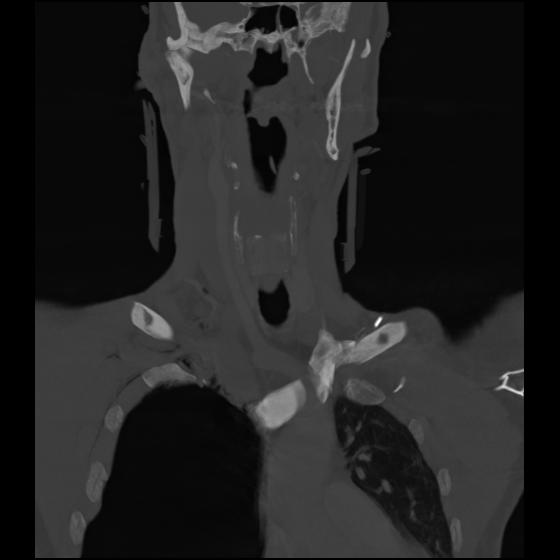

23 ANGIO,CE,Cor-MIP,5.000,ANGIO,Cor-MIP,